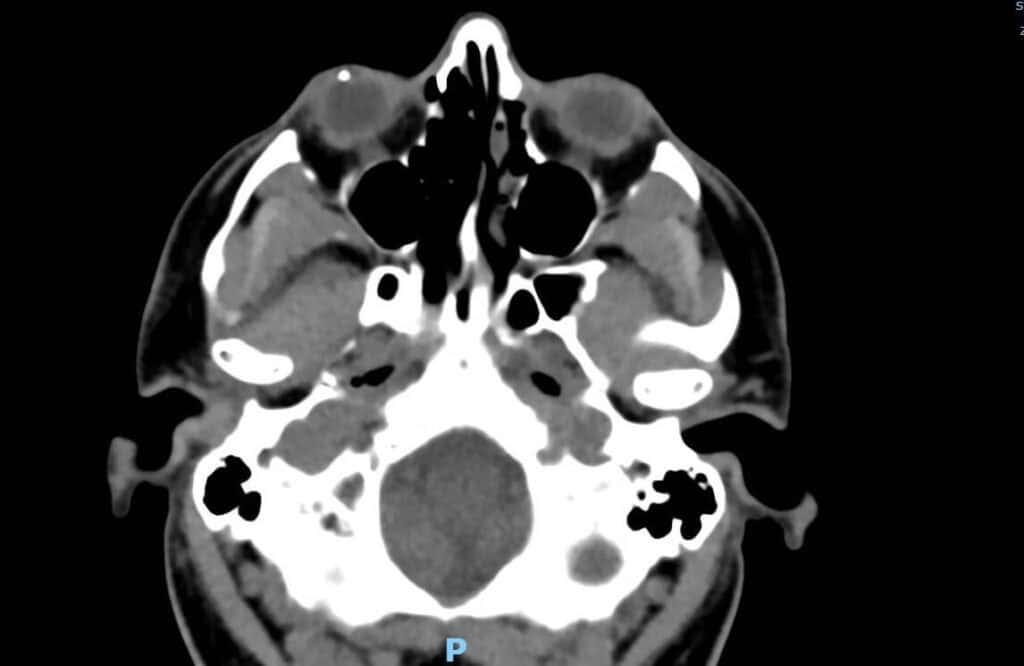

A 40-year-old white male presented to a local ER with the complaint of right eye pain and possible foreign body. He reported he had been hammering nails earlier in the day (without eye protection) and felt something hit his right eye. He rinsed the eye out and continued working. Throughout the day and into the evening his eye got more red and painful, and he reported to the ER for evaluation around 10:30 PM on a Saturday. The ER provider noted reduced vision, a hazy cornea and no external foreign body , so the optometrist on call was consulted for further eye evaluation. The patient’s medical and ocular history were unremarkable. He was up to date on his tetanus vaccine. On exam he was best corrected to 20/200 in the right eye and 20/20 in the left eye. Biomicroscopy of the right eye revealed 2+ conjunctival injection, 2+ diffuse stromal edema, and paracentrally a self-sealed full thickness corneal laceration was noted which was seidel sign negative. Inferiorly within the anterior chamber an approximately 1.5 mm metallic foreign body was noted. CT of the brain/orbits (without contrast) confirmed a metallic foreign body in the anterior chamber of the right eye and no other foreign bodies were noted. (Figure 1)

Figure 1: CT head (without contrast) that shows a metallic foreign body within the anterior chamber of the right eye.